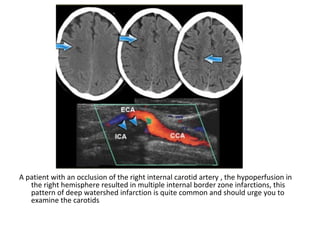

A patient with an occlusion of the right internal carotid artery , the hypoperfusion in

the right hemisphere resulted in multiple internal border zone infarctions, this

pattern of deep watershed infarction is quite common and should urge you to

examine the carotids